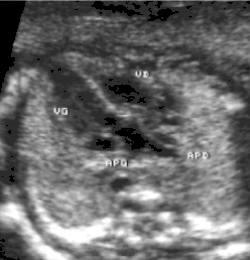

- Les coupes sous costales qui montrent bien le trajet parallèle des gros vaisseaux et leur inversion. Cet examen permettra d'éliminer en particulier un retour veineux pulmonaire anormal total bloqué qui aurait pu rendre compte de l’hypervascularisation pulmonaire sur la radiographie des poumons.